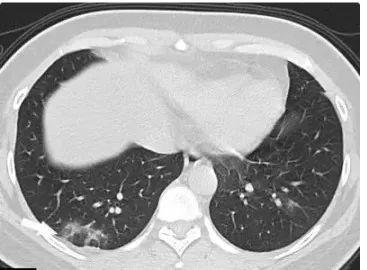

对于新型冠状病毒感,目前现有病例来看,主要的症状是发烧,有低热、甚至高热的现象;干咳为主;三五天之后出现气短、胸闷;有的病人会出现呼吸衰竭、休克的症状。

普通人接触感染者后,从被感染到发病一般不超过14天的潜伏期,一旦被感染,会展现出症状,例如发烧、咳嗽、风寒等日常感冒的常见症状,有这些症状立刻到发热门诊尽快检查。